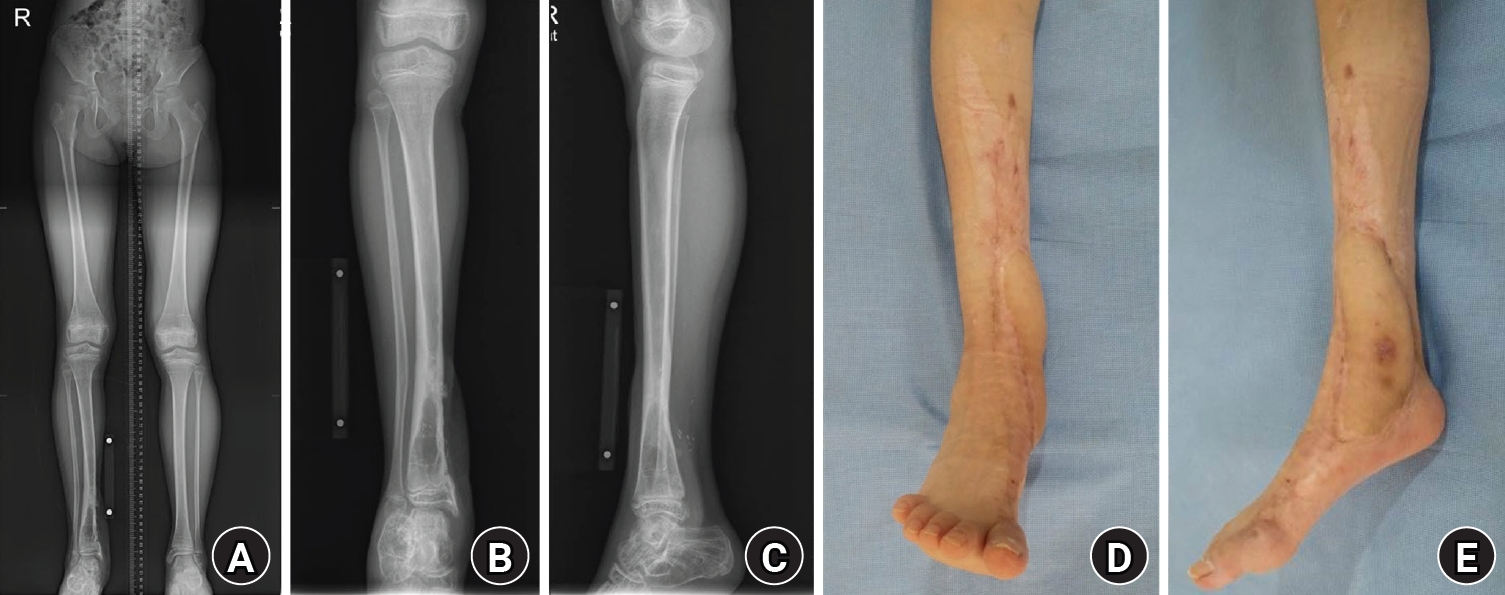

An 8-year-old girl presented after a traffic accident with a severe crush and degloving injury of the medial right ankle and foot, a distal tibiofibular fracture, and medial midfoot bone defects. After staged irrigation and debridement with temporary external fixation, definitive reconstruction was performed on August 6, 2016. The medial malleolar defect (2.5×2.0 cm) was reconstructed using a contoured autologous iliac crest bone graft secured with internal fixation, and medial stability was augmented using harvested gluteal fascia as a deltoid ligament substitute fixed with suture anchors. A bone-cement spacer was placed adjacent to the injured physis to mitigate physeal bridging, and the extensive soft-tissue defect was covered with a free anterolateral thigh flap and skin graft. During follow-up, progressive varus deformity and contracture were managed with corrective osteotomy and plating, Achilles tendon lengthening, Z-plasty, and Ilizarov fixation. At the final follow-up (March 6, 2025), the limb-length discrepancy was 5 mm, active ankle dorsiflexion was 0° (passive dorsiflexion 5°), and the patient was pain-free with full participation in daily activities, including hiking and dancing. This case emphasizes the value of an integrated staged strategy that combines bony reconstruction, medial stabilization, physeal management, and durable soft-tissue coverage during skeletal growth.